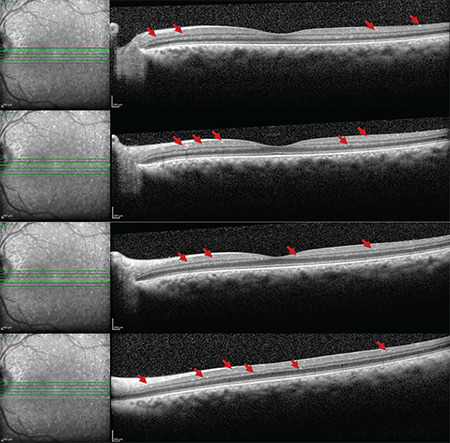

Cystinosis is a rare autosomal recessive lysosomal storage disease associated with high mortality and morbidity rates. The most distinctive ocular manifestations of cystinosis are photophobia, tearing, and blurred vision. Herein, we assessed the ocular involvement of four patients from two families diagnosed with infantile nephropathic cystinosis using optical coherence tomography (OCT) and in vivo confocal microscopy (IVCM). Anterior segment OCT demonstrated multiple hyperreflective punctate deposits, and IVCM revealed needle-shaped bright crystal deposits in the corneal stroma in all patients. Three patients also had crystal deposits in the epithelium, where epithelial cell disruption was observed. Crystal deposits around the subepithelial nerve plexus were noted in some sections. In one patient, round and needle-shaped bright deposits along with inflammatory cells were observed in the limbal region of the conjunctiva. Infrared fundus images of two female siblings revealed hyperreflective crystal-like deposits around the optic disc, macula, and peripheral retina, and enhanced depth imaging OCT showed accumulation of crystals in all layers of the retina.